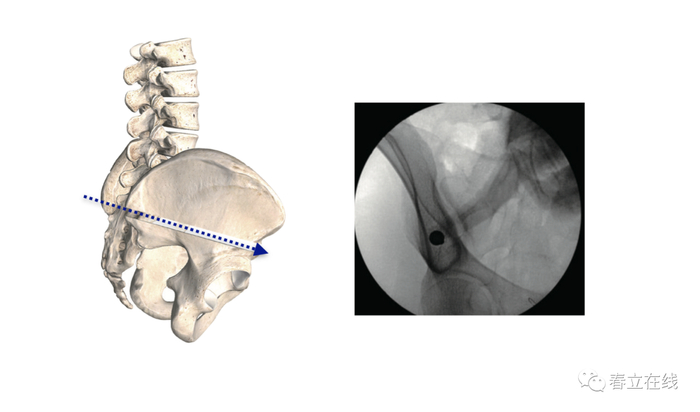

透视确认合适的置钉路径,将C臂机放置在进钉点上方,然后将其向尾端倾斜20—30度。水平倾斜40—50度;对准髂前下棘。此机位下,可在AP位透视上观察到髂骨泪滴。

使用开路器、探针探查。选择的路径方向为水平方向倾斜40—50度,同时向尾端倾斜20—30度,该方向可因骨盆的倾斜和腰椎的前凸的改变而改变。

透视可以确认路径,前后位能够很好的观察到骨盆和坐骨切迹。开路器或钻头在坐骨大切迹内向髂前下棘方向走行不要超过20mm。对骨盆发育异常的病人我们可以选择用开路器来建立通道,以保证安全。

透视泪滴点可以帮助确定钉道在髂骨最后的部分,以免钉道穿破皮质骨。使用探针探查通道并确认终点。注意螺钉长度要与探椎探查的深度及丝攻的深度一致。